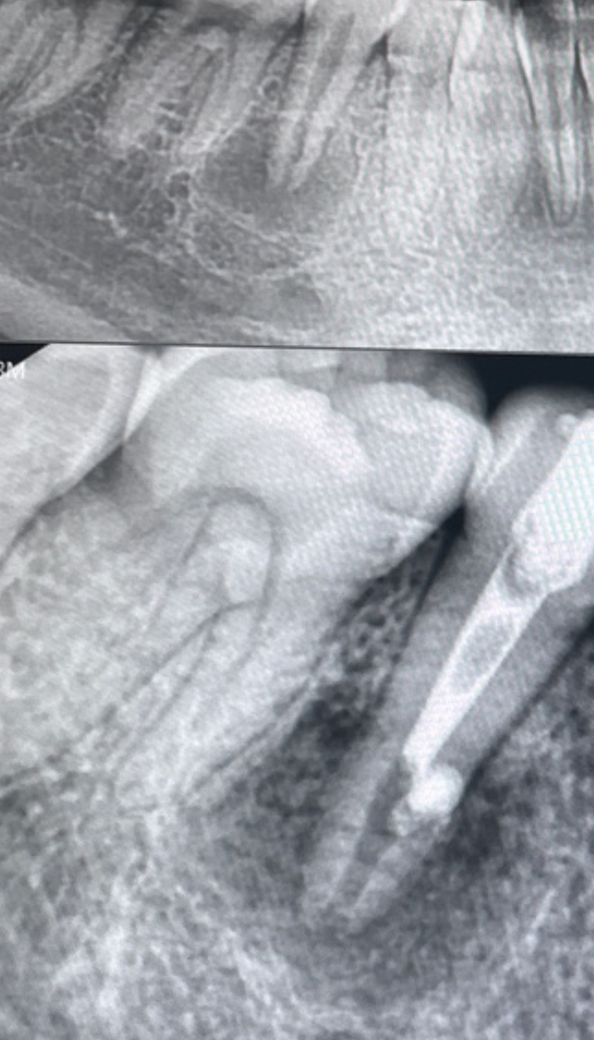

치아 염증 발치 해야할까요ㅠㅠㅠㅠㅠ???

안녕하세요 몇 달 전 치과 검진 차원으로 몇 년만에 치과에 가서 엑스레이를 찍었더니 치아에 큰 염증이 있다고 해서 신경치료를 진행 중 입니다. 저번에 약을 넣고 상태를 봤는데 엑스레이상으로 약이 새어나간 거 같다고 상태가 좋지 않아 발치를 해아할 수도 있을 거 같다 하셨습니다. 지금은 상태를 아직 지켜보는 중이고 8월달에 다시 치과를 가야하는데 며칠째 신경치료 한 이빨 부분이 가끔가다 찌릿한 느낌이 드는데 괜찮은 건지, 정말 발치를 해야하는지, 만약 발치를 한다면 통증은 얼만한지 궁금해요

• 1번 째 사진

엑스레이 상으로도 치아 뿌리끝에 염증이 심한거 같습니다 .신경치료를 여러번 해도 증상이 호전되지 않으면 발치를 하시는게 좋을것같습니다.